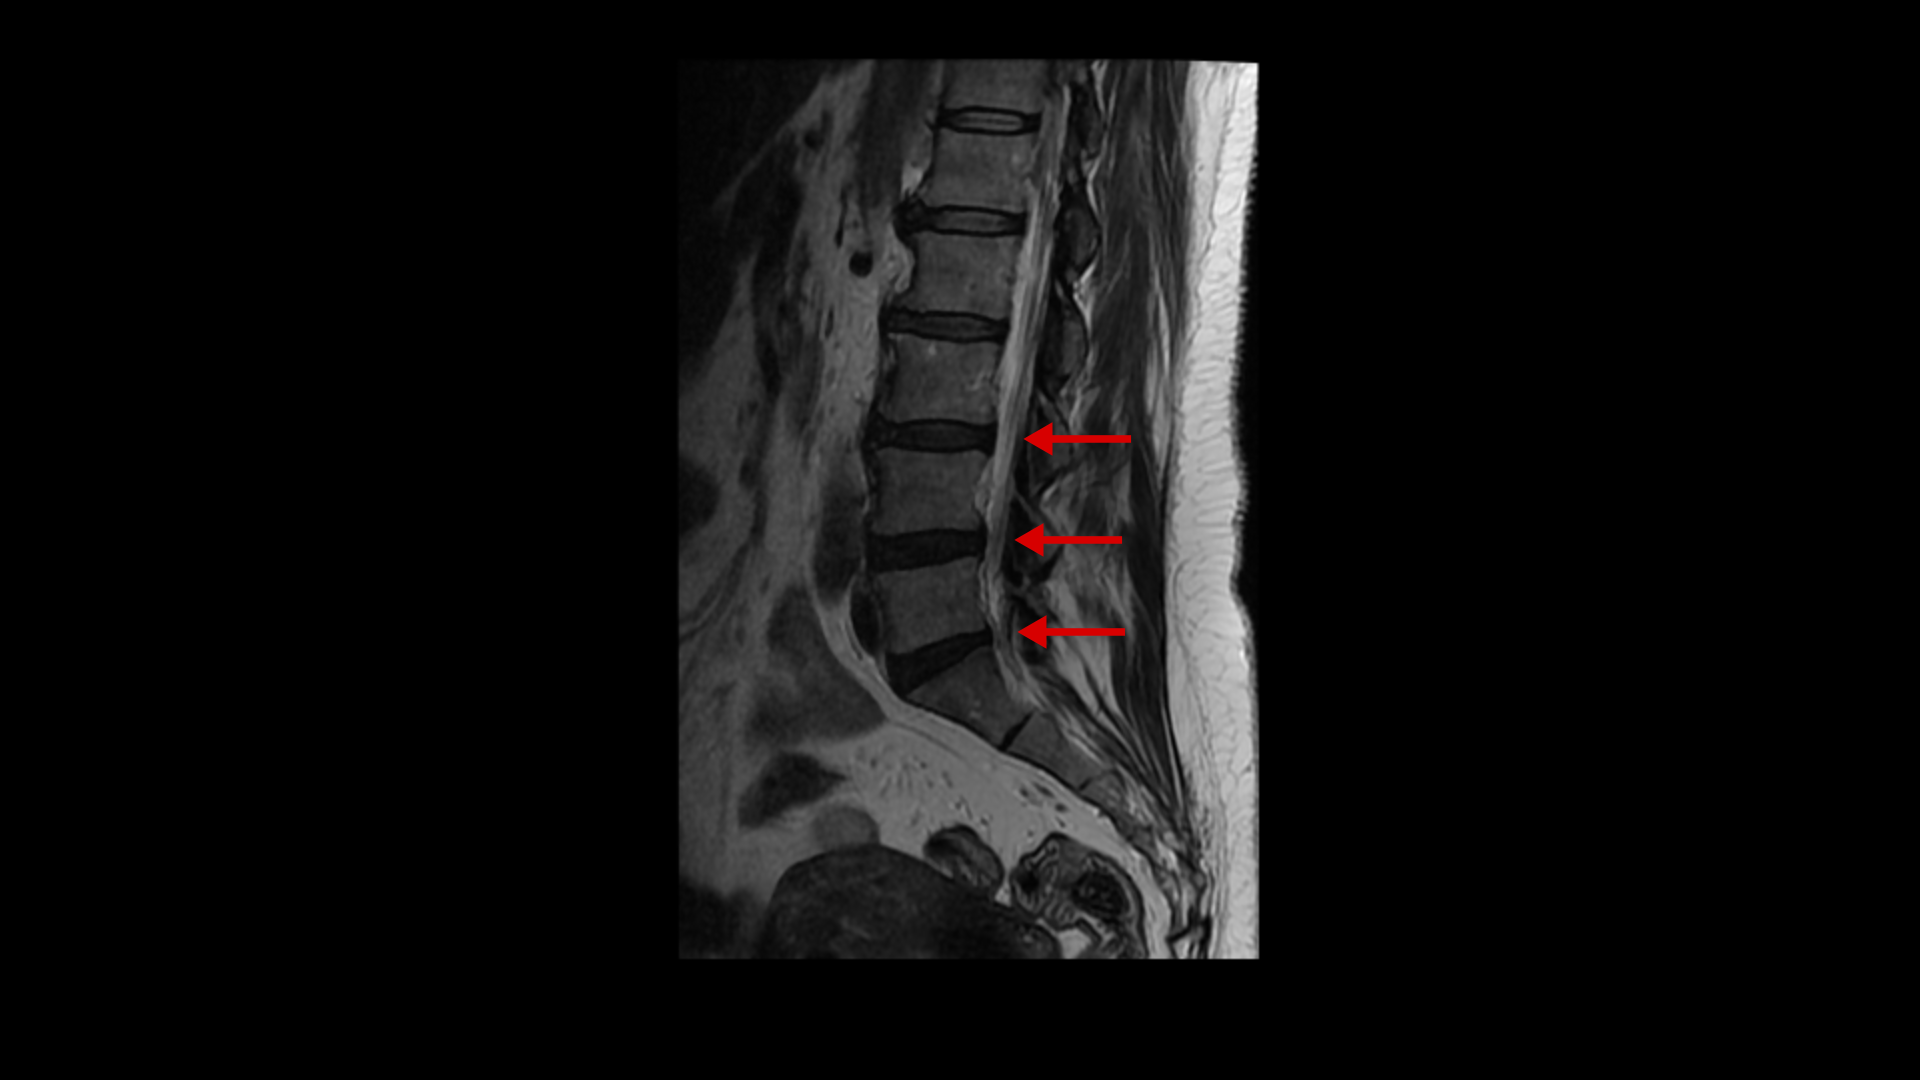

이분 MRI를 보면 퇴행성 변화가 있기는 합니다.

퇴행성 디스크와 디스크 돌출이 있고 황색인대의 비후도 있지만 신경을 심하게 누르는 게 보이지 않기 때문에 양쪽 다리에 감각마비가 올 정도의 심한 신경학적 증상을 일으키기는 어렵다고 봅니다. MRI와 이 환자의 증상이 일치하지 않는 겁니다. 이 환자분의 극심한 증상을 MRI로 설명할 수가 없는 겁니다.

날씨만 안 좋아도 아예 일어서지를 못하셨다고 합니다. 이분처럼 허리와 다리가 저리고 아픈데 MRI에 퇴행성 디스크나 협착이 조금이라도 보이면 거의 대부분 디스크나 협착으로 진단하고 그것을 치료하게 됩니다. 그런데 이분 MRI에서 보시다시피 양쪽 다리에 심한 신경학적 증상을 일으킬만한 병변이 보이지 않습니다. 그래서 반드시 증상과 MRI가 일치하는지 꼼꼼하게 확인하는 게 필요합니다. 진단이 잘못되면 증상의 원인이 아닌 협착증이나 디스크 치료를 한다고 시간만 낭비하고 오랫동안 고생 하기 쉽습니다.